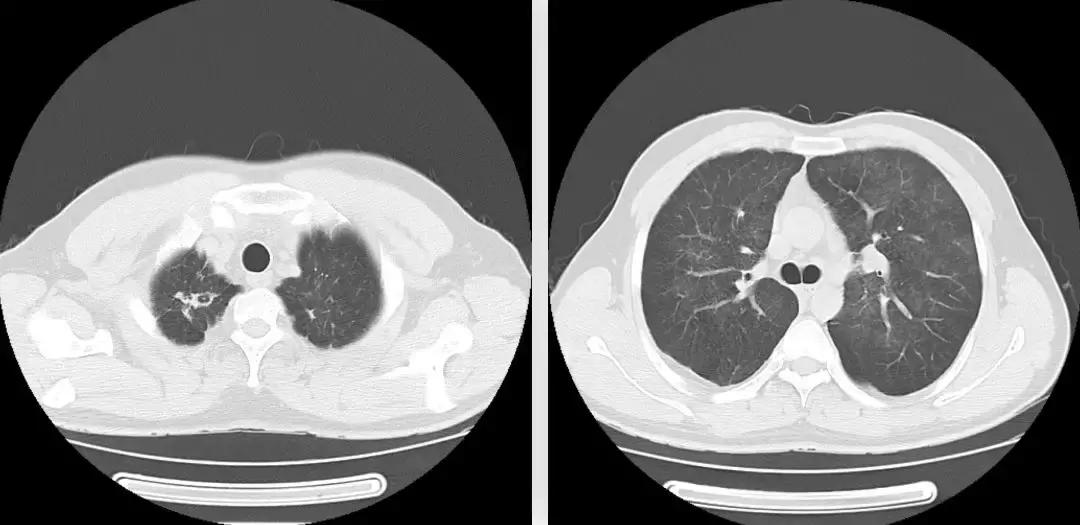

胸部CT(2017-7-31 我院门诊):两肺野弥漫磨玻璃影,性质待定;两肺上叶陈旧性病变。(如下图)

胸部CT(2018-1-18 我院门诊):两肺野弥漫磨玻璃影,较前变化不明显;新增左肺下叶基底段片状密度增高影,建议治疗后复查;两肺上叶陈旧性病变: